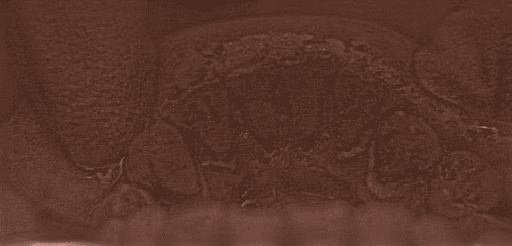

At the organ level, editing difficulty varies significantly. Regions such as the spine and bones (e.g., CT scans) remain especially challenging, with the best EA only reaching 0.38. This difficulty is not primarily due to grayscale input but rather the inherent structural complexity of bones. Unlike soft tissues, bones follow rigid, geometrically consistent patterns (e.g., aligned vertebrae, symmetric ribs), making even small editing errors visually salient and disruptive. For example, in a task like “correct spines”, the model must straighten the spine without disturbing rib symmetry or vertebral alignment, demanding a much higher degree of structural precision than tasks such as “remove intestinal polyps”. The largest performance gaps between Gemini and open-source models are seen in teeth (34%), hands (64%), and gastrointestinal tract (43%), further reflecting the challenges posed by complex anatomical structures and repetitive patterns. Conversely, superficial structures such as hair and nose are easier to edit, where ICEdit achieves strong performance (hair: EA = 0.71, VQ = 0.79).

We then compare the thresholded attention map with the annotated Region-of-Interest (ROI) mask using the Intersection-over-Union: . A higher IoU score indicates stronger spatial alignment between the model’s attention and the intended anatomical target, reflecting better grounding of visual concepts during editing. The average IoU scores for each organ are listed in Tab. 4.

| Organ | IoU | Organ | IoU | Organ | IoU |

| Feet | 0.189 | Teeth | 0.268 | GI Tract | 0.4084 |

| Skin | 0.191 | Face | 0.289 | Hands | 0.409 |

| Nose | 0.193 | Bones | 0.389 | Hair | 0.497 |

| Eyes | 0.195 | Ears | 0.407 | Torso | 0.592 |

| Mouth | 0.224 | - | - | - | - |